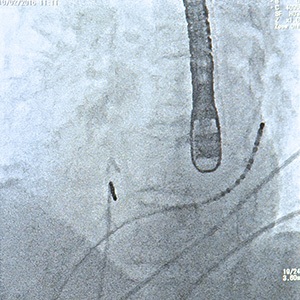

Cardioversion is a medical procedure by which an abnormal heart rhythm is returned to normal (sinus) rhythm. This can be achieved with medications (anti-arrhythmics) or with an electrical shock under anaesthesia. They are performed as required by our cardiologists.

A TOE is a procedure that uses ultrasound imaging of the heart. Under light sedation a transducer is swallowed, passing into the oesophagus (or food tube). This enables an often clearer view of the structures and function of the heart. These are arranged by individual cardiologists as required. This is often performed with a Cardioversion.